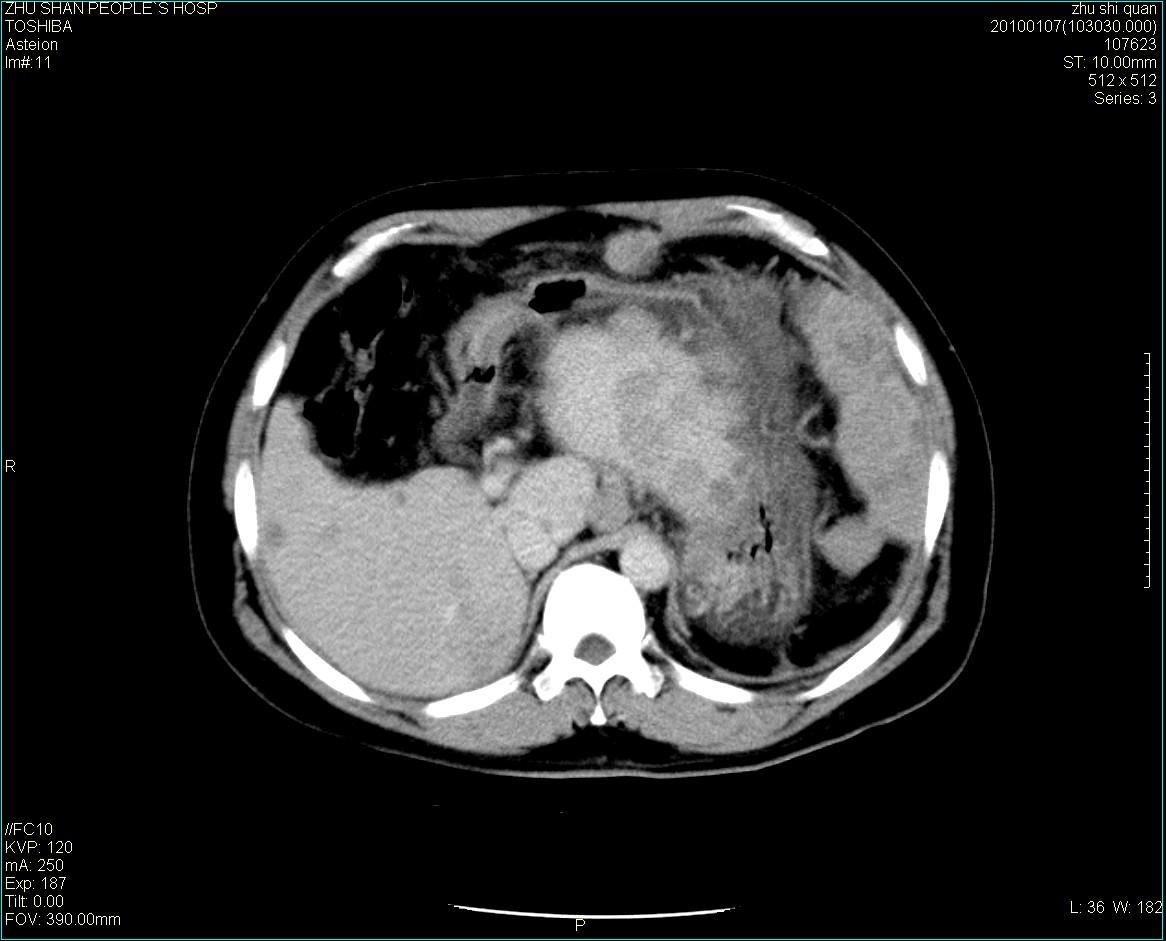

男性病人 肝ca两次术后,今日复查。

多发转移

肝、脾多发转移灶,胸腔积液

1)肝癌并多发性转移。2)双侧胸腔积液(以左侧为甚)伴左下部分肺萎陷。

肝癌术后复发,考虑肝、脾多发转移。

肝癌术后复发,肝内、脾脏、腹膜后及腹膜多发转移,腹水,双侧胸腔积液(以左侧为甚)伴左下膨胀不全。

肝、脾多发转移灶,胸腔积液。

肝癌术后复发,肝内、脾脏、腹膜后及腹膜多发淋巴结转移,腹水,双侧胸腔积液。